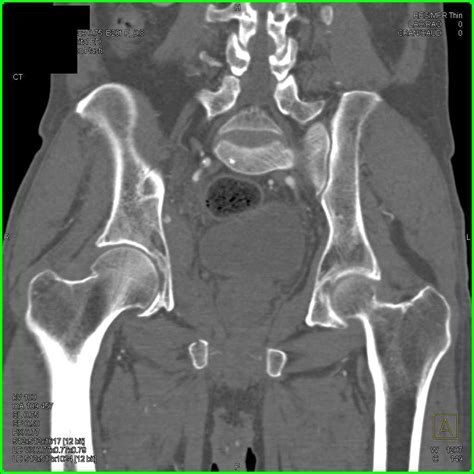

Diagnosing Hip Joint Effusion

Diagnosing hip joint effusion typically involves a combination of physical examination, medical history, and diagnostic tests. The diagnostic process may include:

• Imaging Tests: X-rays, MRI, or ultrasound to visualize the hip joint and detect fluid accumulation.